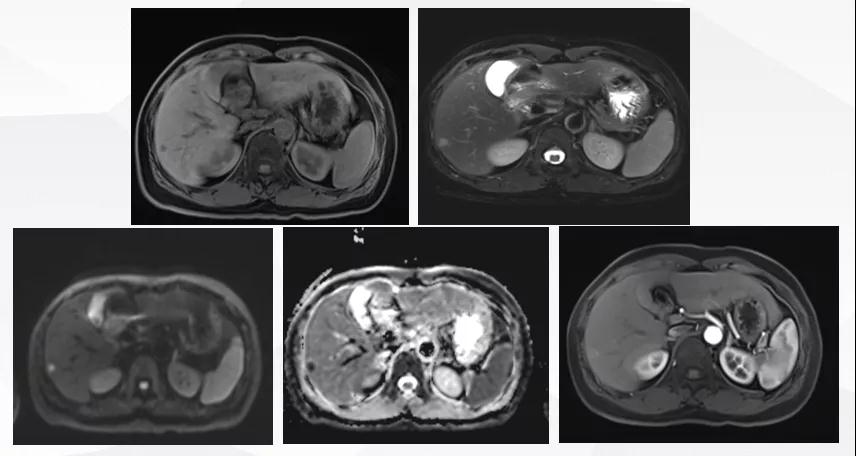

给予T-DM1治疗。治疗6个月后复查MR显示脑、肝、骨转移瘤均较前明显缩小,达到部分缓解(PR)(图2)。目前PFS已达10+个月。

图2

患者为ⅢA期(cT3N1M0)、三阳性乳腺癌,经AC-TH新辅助治疗达到降期(ypT2N0M0)。患者内分泌+抗HER2辅助治疗结束6个月时出现转移进展(脑、肝、骨),给予THP一线治疗,因无法耐受毒副作用而改为T-DM1,治疗6个月达到肝、脑、骨转移PR,患者目前中位PFS已超过10个月,T-DM1治疗过程中仅出现轻度CIT,且可自行恢复。